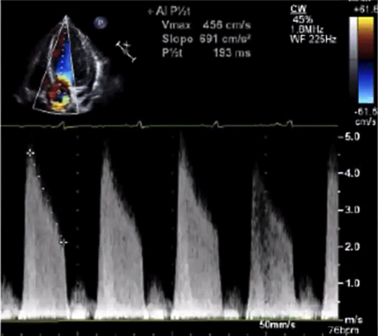

# Doppler Echo Evaluation of MVR 二尖瓣人工瓣膜

- Peak early velocity 峰值早期速度

- Mean pressure gradient 平均压差

- Heart rate at time of Doppler 多普勒检查时的心率

- Pressure Half-time 压力减半时间

- Doppler velocity index:

- Presence, location and severity of regurgitation

反流的存在、位置和严重程度 - Effective orifice area 有效瓣口面积

# Doppler Parameters of Prosthetic Mitral Valve Stenosis 狭窄的指标

| Normal | Possible Stenosis | Suggests Sigificant Stenosis | |

|---|---|---|---|

| Peak velocity | < 1.9 m/s | 1.9-2.5 m/s | ≥ 2.5 m/s |

| Mean gradienty | ≤ 5 mmHg | 6-10 mmHg | > 10 mmHg |

| VTIPrMV / VTILVO | < 2.2 | 2.2-2.5 | > 2.5 |

| EOA | ≥ 2.0 cm2 | 1-2 cm2 | < 1cm2 |

| PHT | < 130 ms | 130 - 200 ms | > 200 ms |